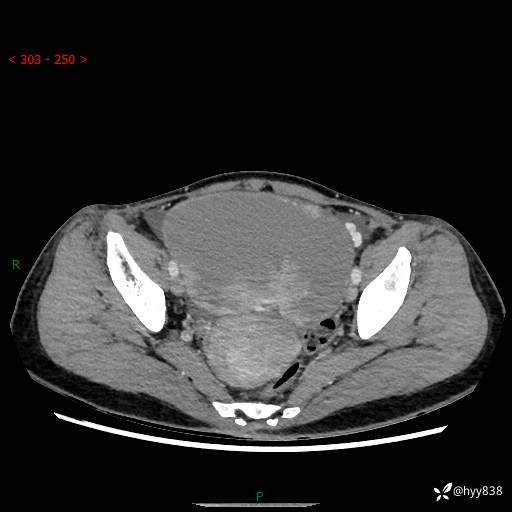

【患者信息】:女,50岁

【主诉】:外院超声发现腹盆肿块,为进一步诊治来我院,门诊已“盆腔肿块”收入院。

腹盆CT平扫+增强

【临床诊断】:盆腔肿瘤